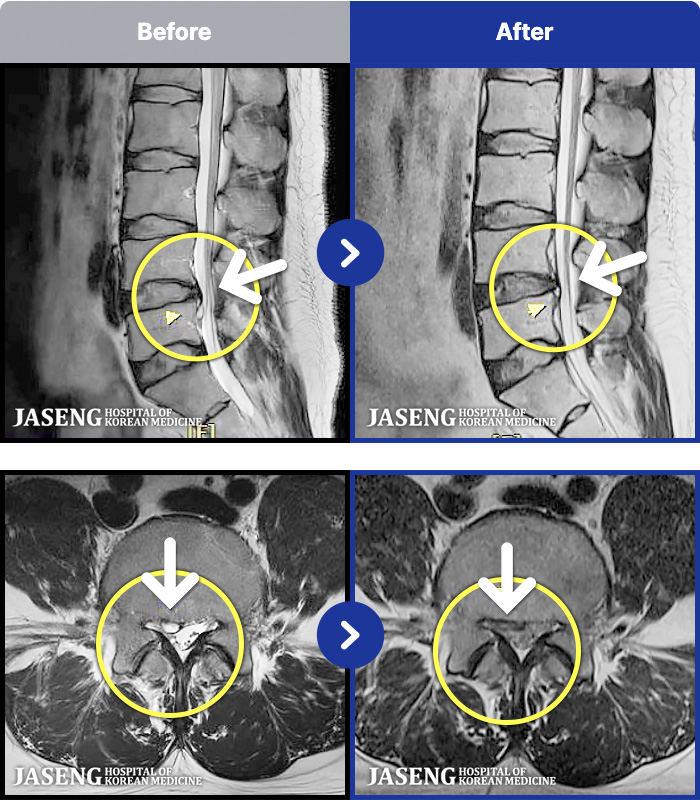

1,237 MRI ũ ʸ Ȯϼ.

1,237